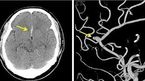

[OSEN=이슈팀] 뇌동맥류 환자가 급증해 장안의 화제가 되고 있다. 최근 날씨가 부쩍 추워지면서 뇌동맥류 등 뇌혈관질환으로 병원을 찾은 환자가 늘어난 사실이 발표되면서 누리꾼들의 관심이 쏠리고 있다. 뇌동맥류 환자 급증